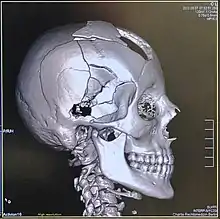

Head

CT scanning of the head is typically used to detect infarction (stroke), tumors, calcifications, haemorrhage, and bone trauma.[32] Of the above, hypodense (dark) structures can indicate edema and infarction, hyperdense (bright) structures indicate calcifications and haemorrhage and bone trauma can be seen as disjunction in bone windows. Tumors can be detected by the swelling and anatomical distortion they cause, or by surrounding edema. CT scanning of the head is also used in CT-guided stereotactic surgery and radiosurgery for treatment of intracranial tumors, arteriovenous malformations, and other surgically treatable conditions using a device known as the N-localizer.[33][34][35][36][37][38]